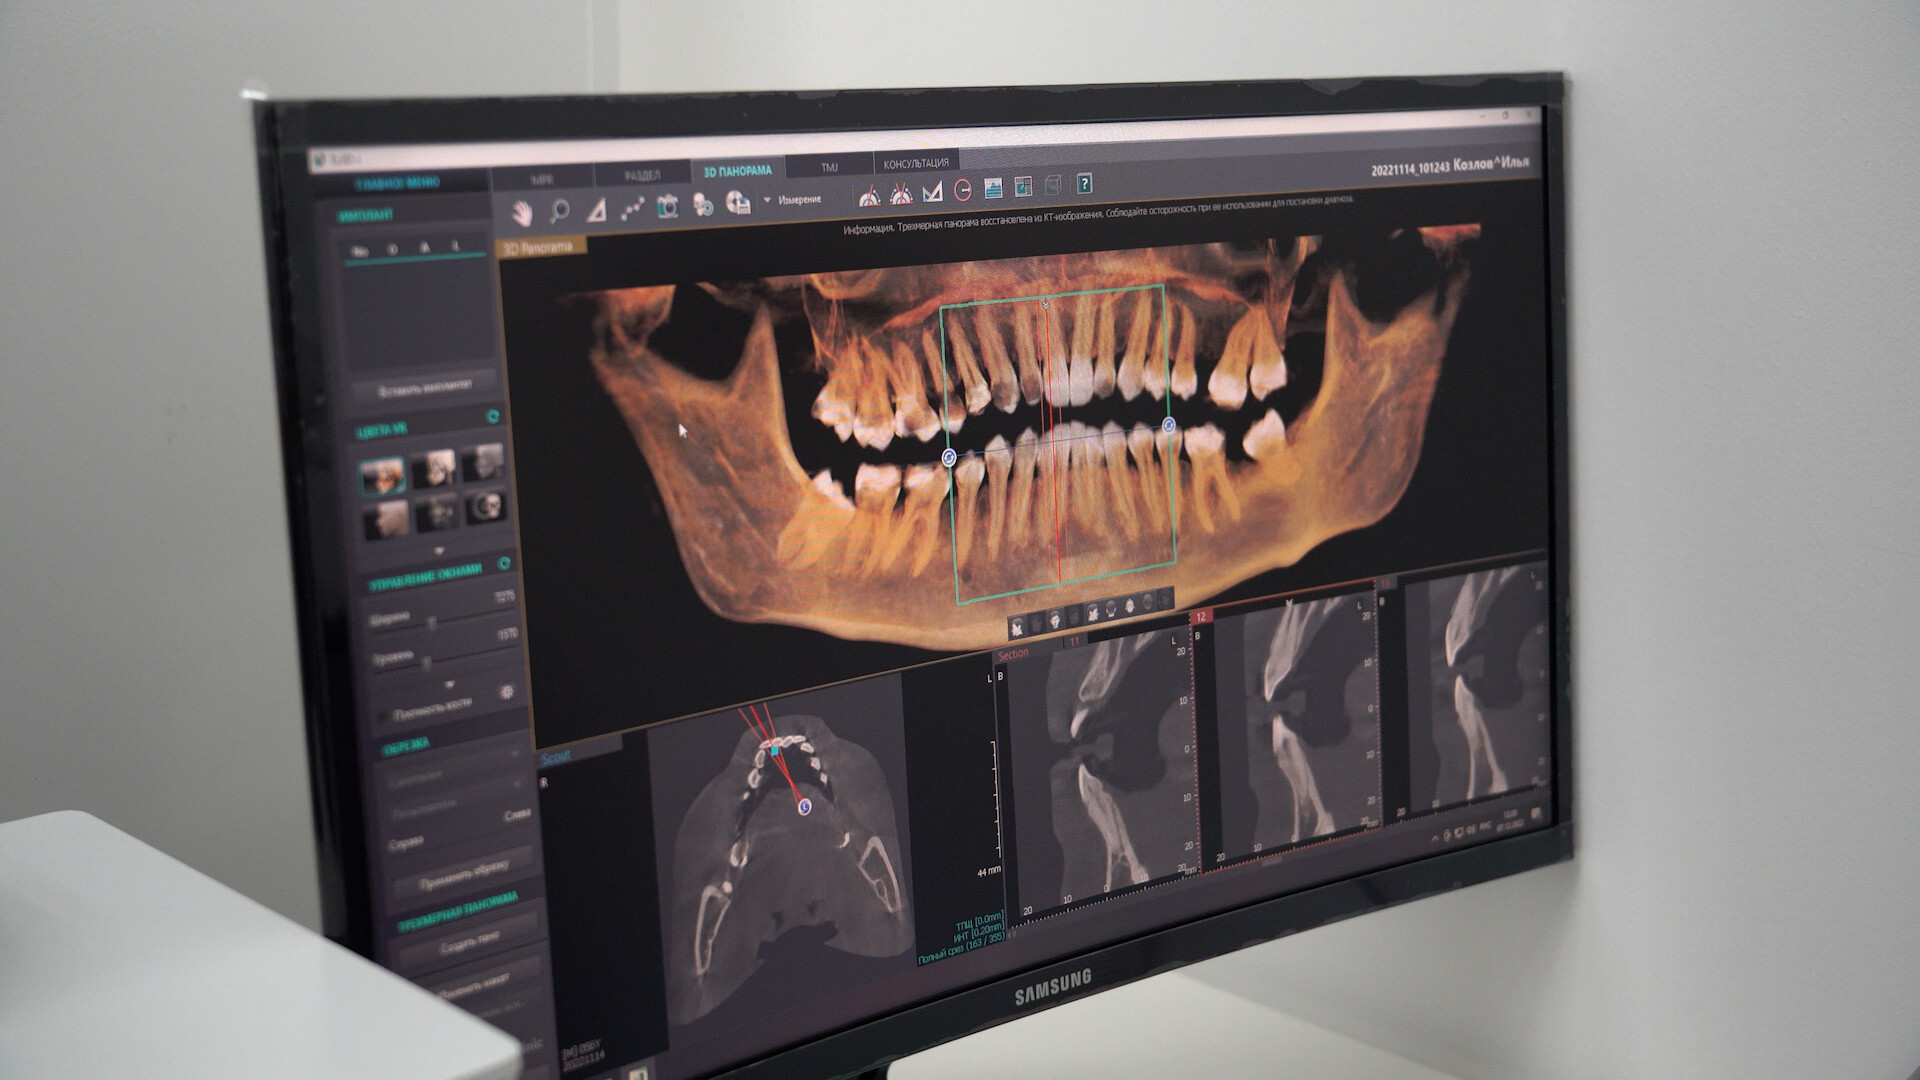

Добро пожаловать на сайт нашей цифровой стоматологической клиники! Мы рады предложить вам широкий спектр услуг по уходу за полостью рта. Наша клиника оснащена самым современным оборудованием, что позволяет нам предоставлять высококачественные услуги в комфортной и безопасной обстановке.

Составим индивидуальный план лечения с использованием новейших цифровых технологий

ИМПЛАНТАЦИЯ

ИМПЛАНТАЦИЯ

Имплантация – один из методов восстановления отсутствующих зубов в зубном ряду, сохраняющий внешний вид и жевательную способность челюсти.

ДИАГНОСТИКА

Лечение любых патологий требует выявления причин ее развития, клинической картины и анатомических особенностей пораженной зоны организма. Стоматология, как и любое направление медицины, не может обойтись без диагностических обследований.

В нашем стоматологическом центре оказываются услуги комплексной диагностики зубов с применением инновационных методик, новейших технологий и современного оборудования

СТОИМОСТЬ ИМПЛАНТАЦИИ

Компьютерная томография

/КЛКТ..................................................................................................от 1 950 р.